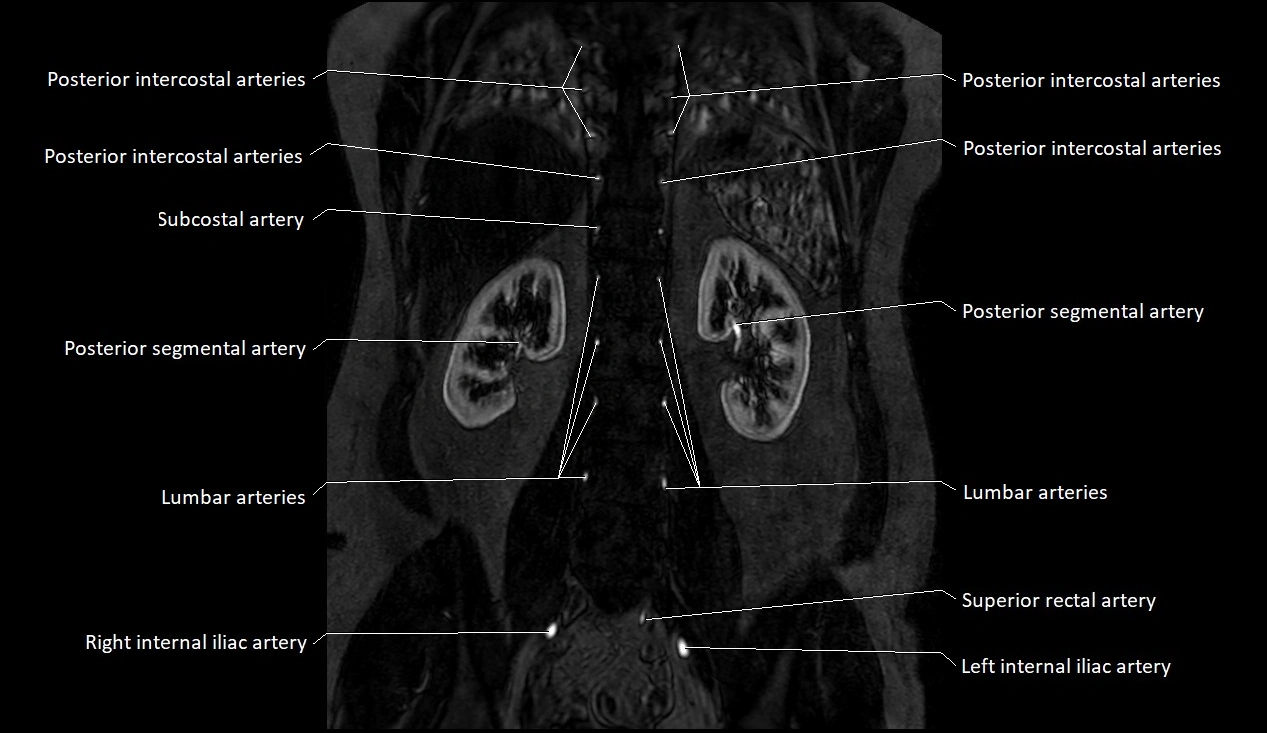

MRI images

image